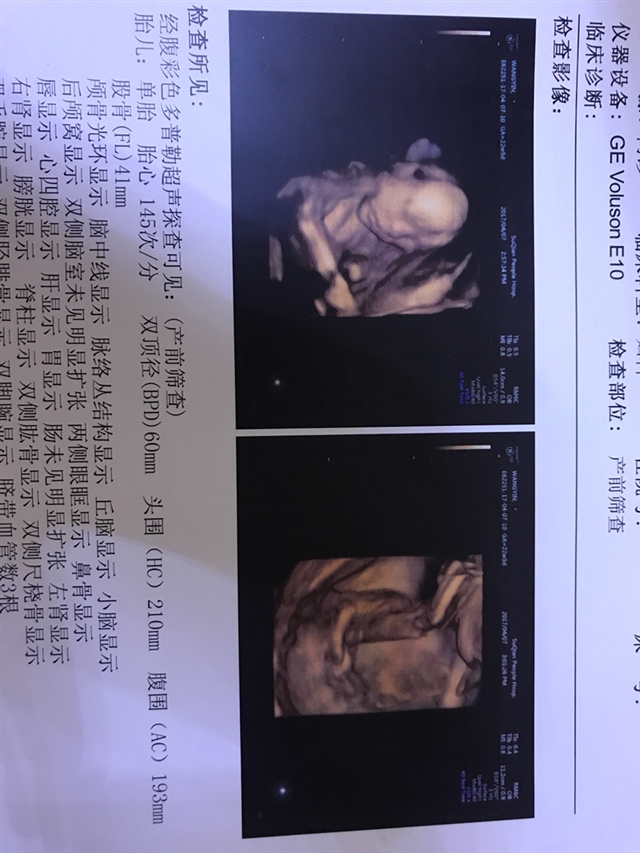

产前检查 B超